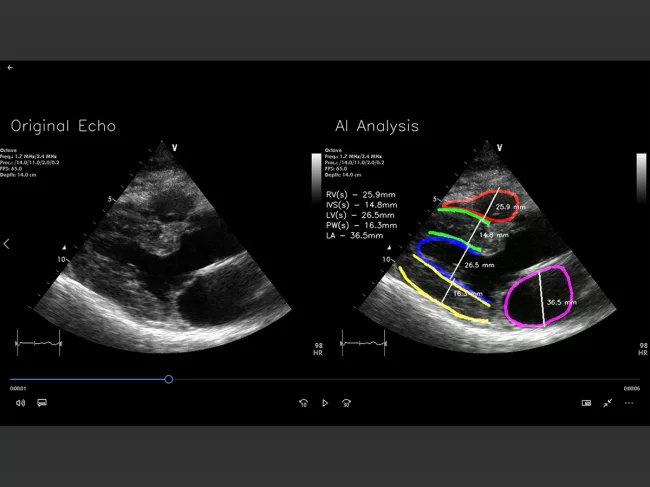

Software screenshot

Rsip Vision develops algorithmic module for heart function assessment

HONG KONG – A new algorithmic module developed by Rsip Vision Ltd. makes it possible to generate automated expert-level assessment of heart functions, facilitating quick and reliable detection of cardiac illness and heart attacks. Read More